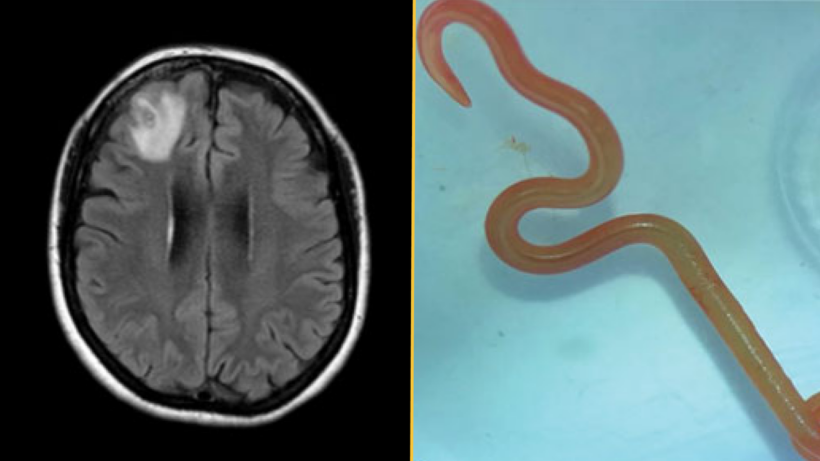

Диагноз: Примерно через год после первого обращения в больницу у женщины начали появляться признаки депрессии и случались эпизоды забывчивости. Врачи назначили МРТ головного мозга и обнаружили очаг поражения в правой лобной доле. Затем они провели открытую биопсию, чтобы обнажить и исследовать поврежденный участок. Именно тогда они обнаружили «структуру, напоминающую нить» внутри этого очага, которую идентифицировали как живого паразитического червя — гельминта, согласно отчету о ее случае.

Червь был ярко-красного цвета, длиной около 3 дюймов (80 мм) и толщиной 0,04 дюйма (1 мм).

В чем уникальность случая: Врачи идентифицировали гельминта как личинку третьей стадии Ophidascaris robertsi — вида паразитических нематод, эндемичных для Австралии. Взрослые черви размножаются внутри ковровых питонов (Morelia spilota), но на личиночных стадиях своего жизненного цикла нематода может заражать других животных.